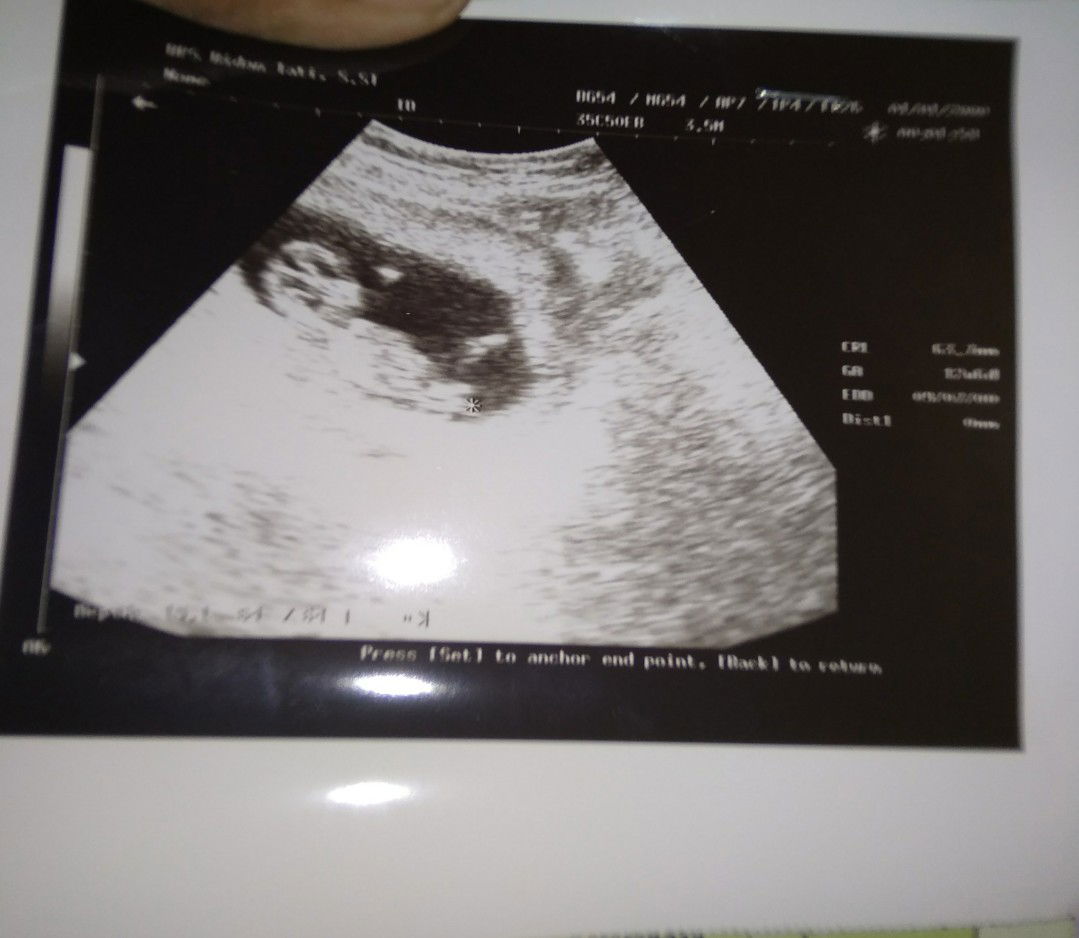

sedang mengandung

Alhamdulillah

Assalamualaikum Bunda allhamdulilah baru jalan 4 bulan tapi perut udh keliatan kaya udh 4 bulan udh jelas???